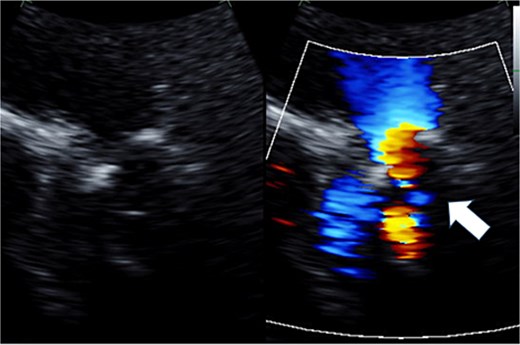

Preoperative transthoracic echocardiography: severe tricuspid regurgitation. The regurgitant jet is indicated by the white arrow.